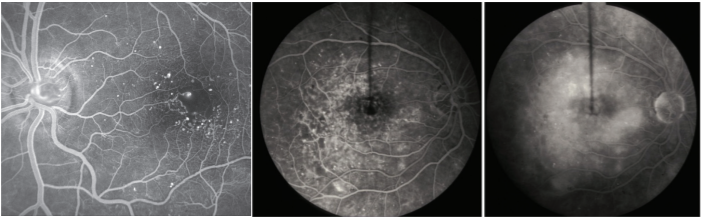

Fluorescein angiography (Figure 1) and optical coherence tomography (OCT; Figure 2) are 2 common tests to evaluate macular edema. Based on the appearance of fluid on these tests, macular edema may be widespread, localized, or be made up of many small blisters surrounding the center of the macula—a common form called cystoid macular edema.